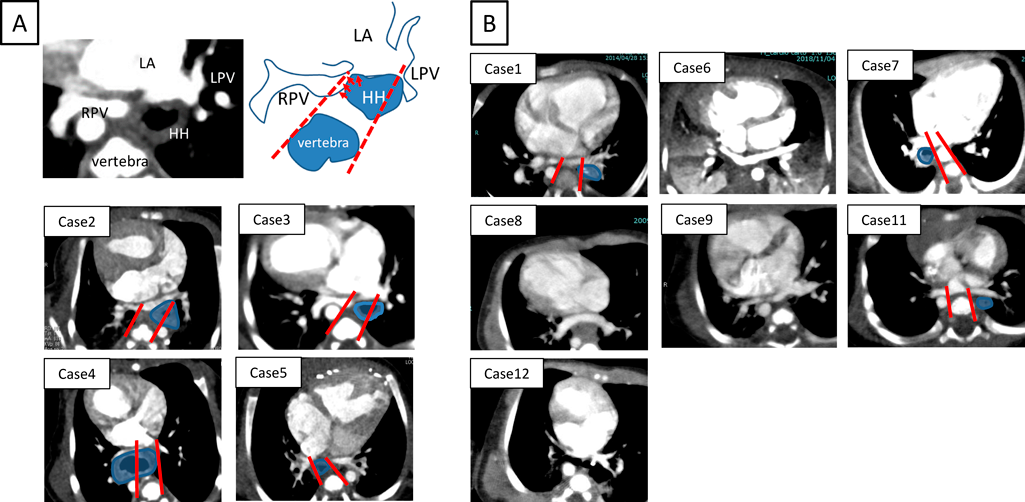

HH手術施行6例中肺静脈圧排が疑われHH手術を行った4例は,いずれも胸部CT検査で滑脱した胃による肺静脈圧排解除が確認された.そのうちの1例(症例4)の画像を提示する(Fig. 1).出生時の胸部CTで滑脱した胃が右下肺静脈を圧排しており(Fig. 1A, B),5ヵ月時の胸部CTで右下肺静脈閉塞を来していた(Fig. 1C, D).この段階での滑脱した胃による直接的な右下肺静脈圧排はないものの,以前認められた右下肺静脈圧排や,滑脱した胃による胸腔内容量の減少,心臓の位置変化が右下肺静脈閉塞の要因として否定できなかったことに加え,その時点で滑脱した胃が接していた左下肺静脈が圧排され閉塞することが危惧されたためHH修復術の適応とされた.HH修復術施行後の胸部CTでは左肺静脈圧排が解除されたのみならず,右肺静脈閉塞も改善していた(Fig. 1E, F).また,重度の胃食道逆流によりHH手術の適応となった1例は,術前から行っていたEDチューブによる経管栄養を術後に離脱することができ,左房後方スぺース確保目的にHH手術を行った1例ではTAPVC修復術を施行可能となった.

Fig. 1 Chest CT images of case 4

A, B: 14 days old. The right Lower pulmonary vein (white arrow) is compressed by hiatal hernia (HH, red dotted circle). C, D: 5 months old. The right lower pulmonary vein obstruction (PVO) due to compression by HH was detected. The HH moved to the back of the left pulmonary vein. E, F: Post HH operation. The PVO was not detected. After confirming this finding, BDG was performed.

滑脱した胃と肺静脈との位置関係(Figs. 4, 5)

胸部CT画像における滑脱した胃と肺静脈との位置関係の相違を,肺静脈圧排例と非圧排例で観察し比較した.13例全例において肺静脈は共通肺静脈腔を形成し心房に接続していた.肺静脈圧排群(症例2, 3, 4, 5)では,①滑脱した胃の先進部が共通肺静脈腔と同じ高さに達している,②滑脱した胃は必ず心房椎体間に位置し,肺静脈を後方から圧排している,といった特徴を有していた.なお,下行大動脈は肺静脈圧排に関与していなかった.一方で肺静脈非圧排群では,①滑脱した胃の先進部が共通肺静脈腔の高さに達していない例(症例6, 8, 9, 12)と,②滑脱した胃の先進部が共通肺静脈腔の高さに達していても,共通肺静脈腔よりも末梢に位置している例(症例1, 7, 11)があった.肺静脈圧排群と非圧排群の特徴は,椎体の両縁から左右の肺静脈開口部へそれぞれ線を引き,その線の間に滑脱した胃が含まれるかどうかでより明確に判断できた(Fig. 4A).肺静脈圧排群では滑脱した胃は同線の間に位置した(Fig. 4A).一方で非圧排群では,滑脱した胃は同線外側に位置するか,肺静脈心房開口部とは同じCT断面で観察されず肺静脈開口部よりも腹側に位置していた(Fig. 4B).

Fig. 4 Chest CT images of all cases

If the pulmonary vein and hiatal hernia (HH) are in the same cross-section, the round shows HH (Case 1–5, 7, 11). A: In case 2–5, the pulmonary vein compression is observed. B: In case 1, 6–9, 11–12, the pulmonary vein compression is not observed.